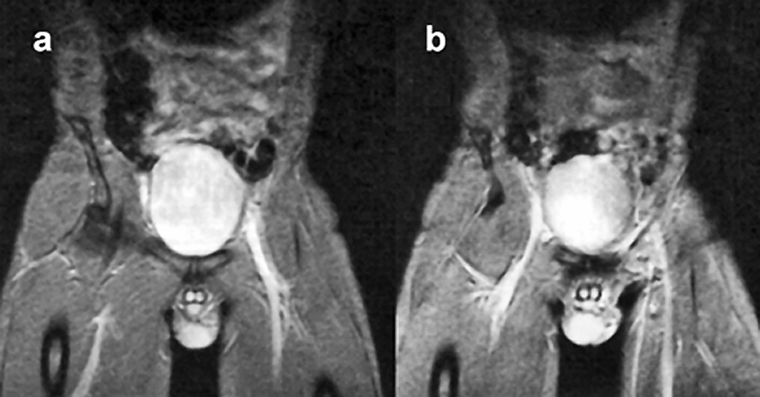

Figure 14-10 shows that in the spin-echo image, flowing blood within the heart cham­bers and the ascending aorta is black, whereas in the gradient-echo image, flow­­ing blood appears bright.

Figura 14-10:

Effects of blood flow upon signal intensity in a (a) spin-echo and a (b) gradient-echo pulse sequence.